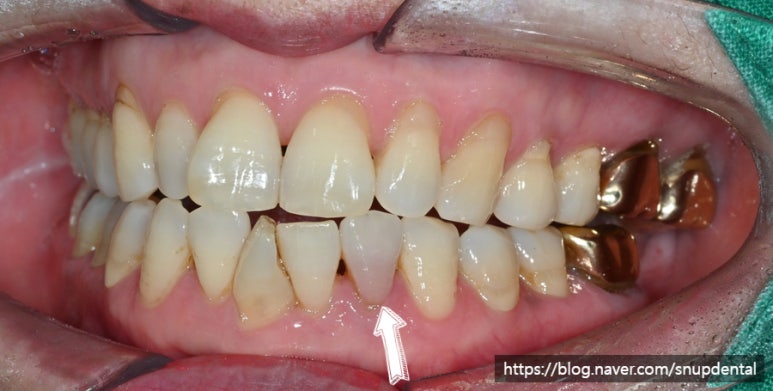

제주 서울업치과에서 크라운 치료를 받으신 환자분께서 아래 앞니 치아색이 변했다고 내원하셨습니다.

왼쪽 아래 두 번째 앞니(#32)

충혈(hyperemia) 증상

차가운 물 및 뜨거운 물에 통증이 있으셨다 함.

두드리거나(percussion test), 솜을 물었을 때(bite test) 통증.

위와 같이 치아 색이 변하는 경우는 치수 충혈 증상으로 볼 수 있으며 우식에 의한 치수염이나 외상에 의한 충격 시에 나타날 수 있습니다.

단순히 색만 변한 경우에는 지켜보는 경우도 있으나 위 환자의 경우 치수염 증상이 나타났고 비가역적 치수염으로 자연적으로 회복이 불가능하다고 판단되어 근관치료(신경치료)를 진행하였습니다.

내부 치수 및 변색 상아질을 제거하고 근관치료를 할 경우 위와 같은 색변화는 대부분 없어집니다만, 혹시나 필요할 경우 실활치 미백(walking bleeching)을 진행하는 경우도 있습니다.

주변 치질이 건전하기에 우선 근관치료 후 레진으로 마무리할 예정입니다.